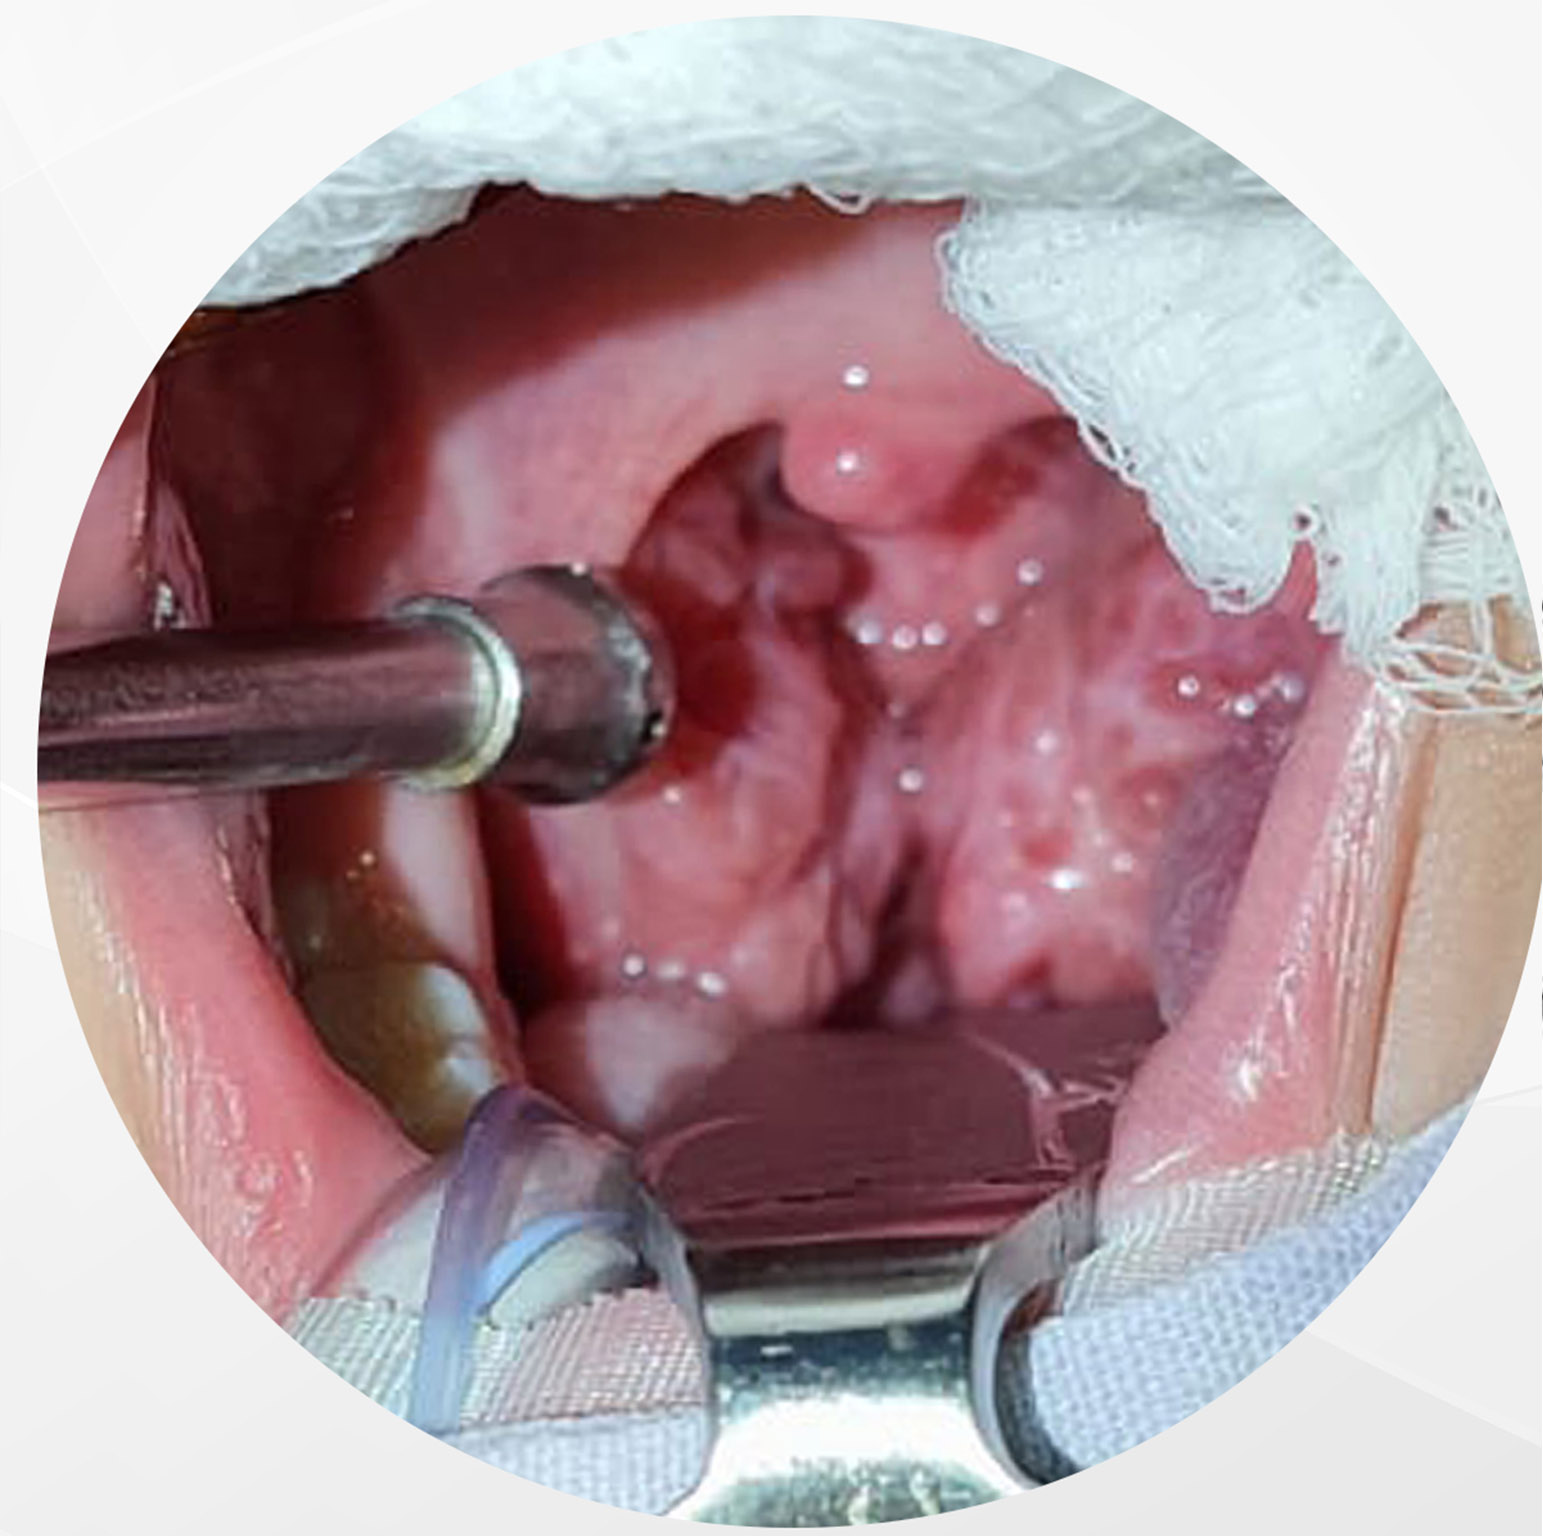

Es una cirugía que frecuentemente se realiza en niños roncadores, respiradores orales que presentan crecimiento exagerado de las amígdalas palatinas o anginas así como las adenoides ( tejido linfoide que crece atrás de la nariz)